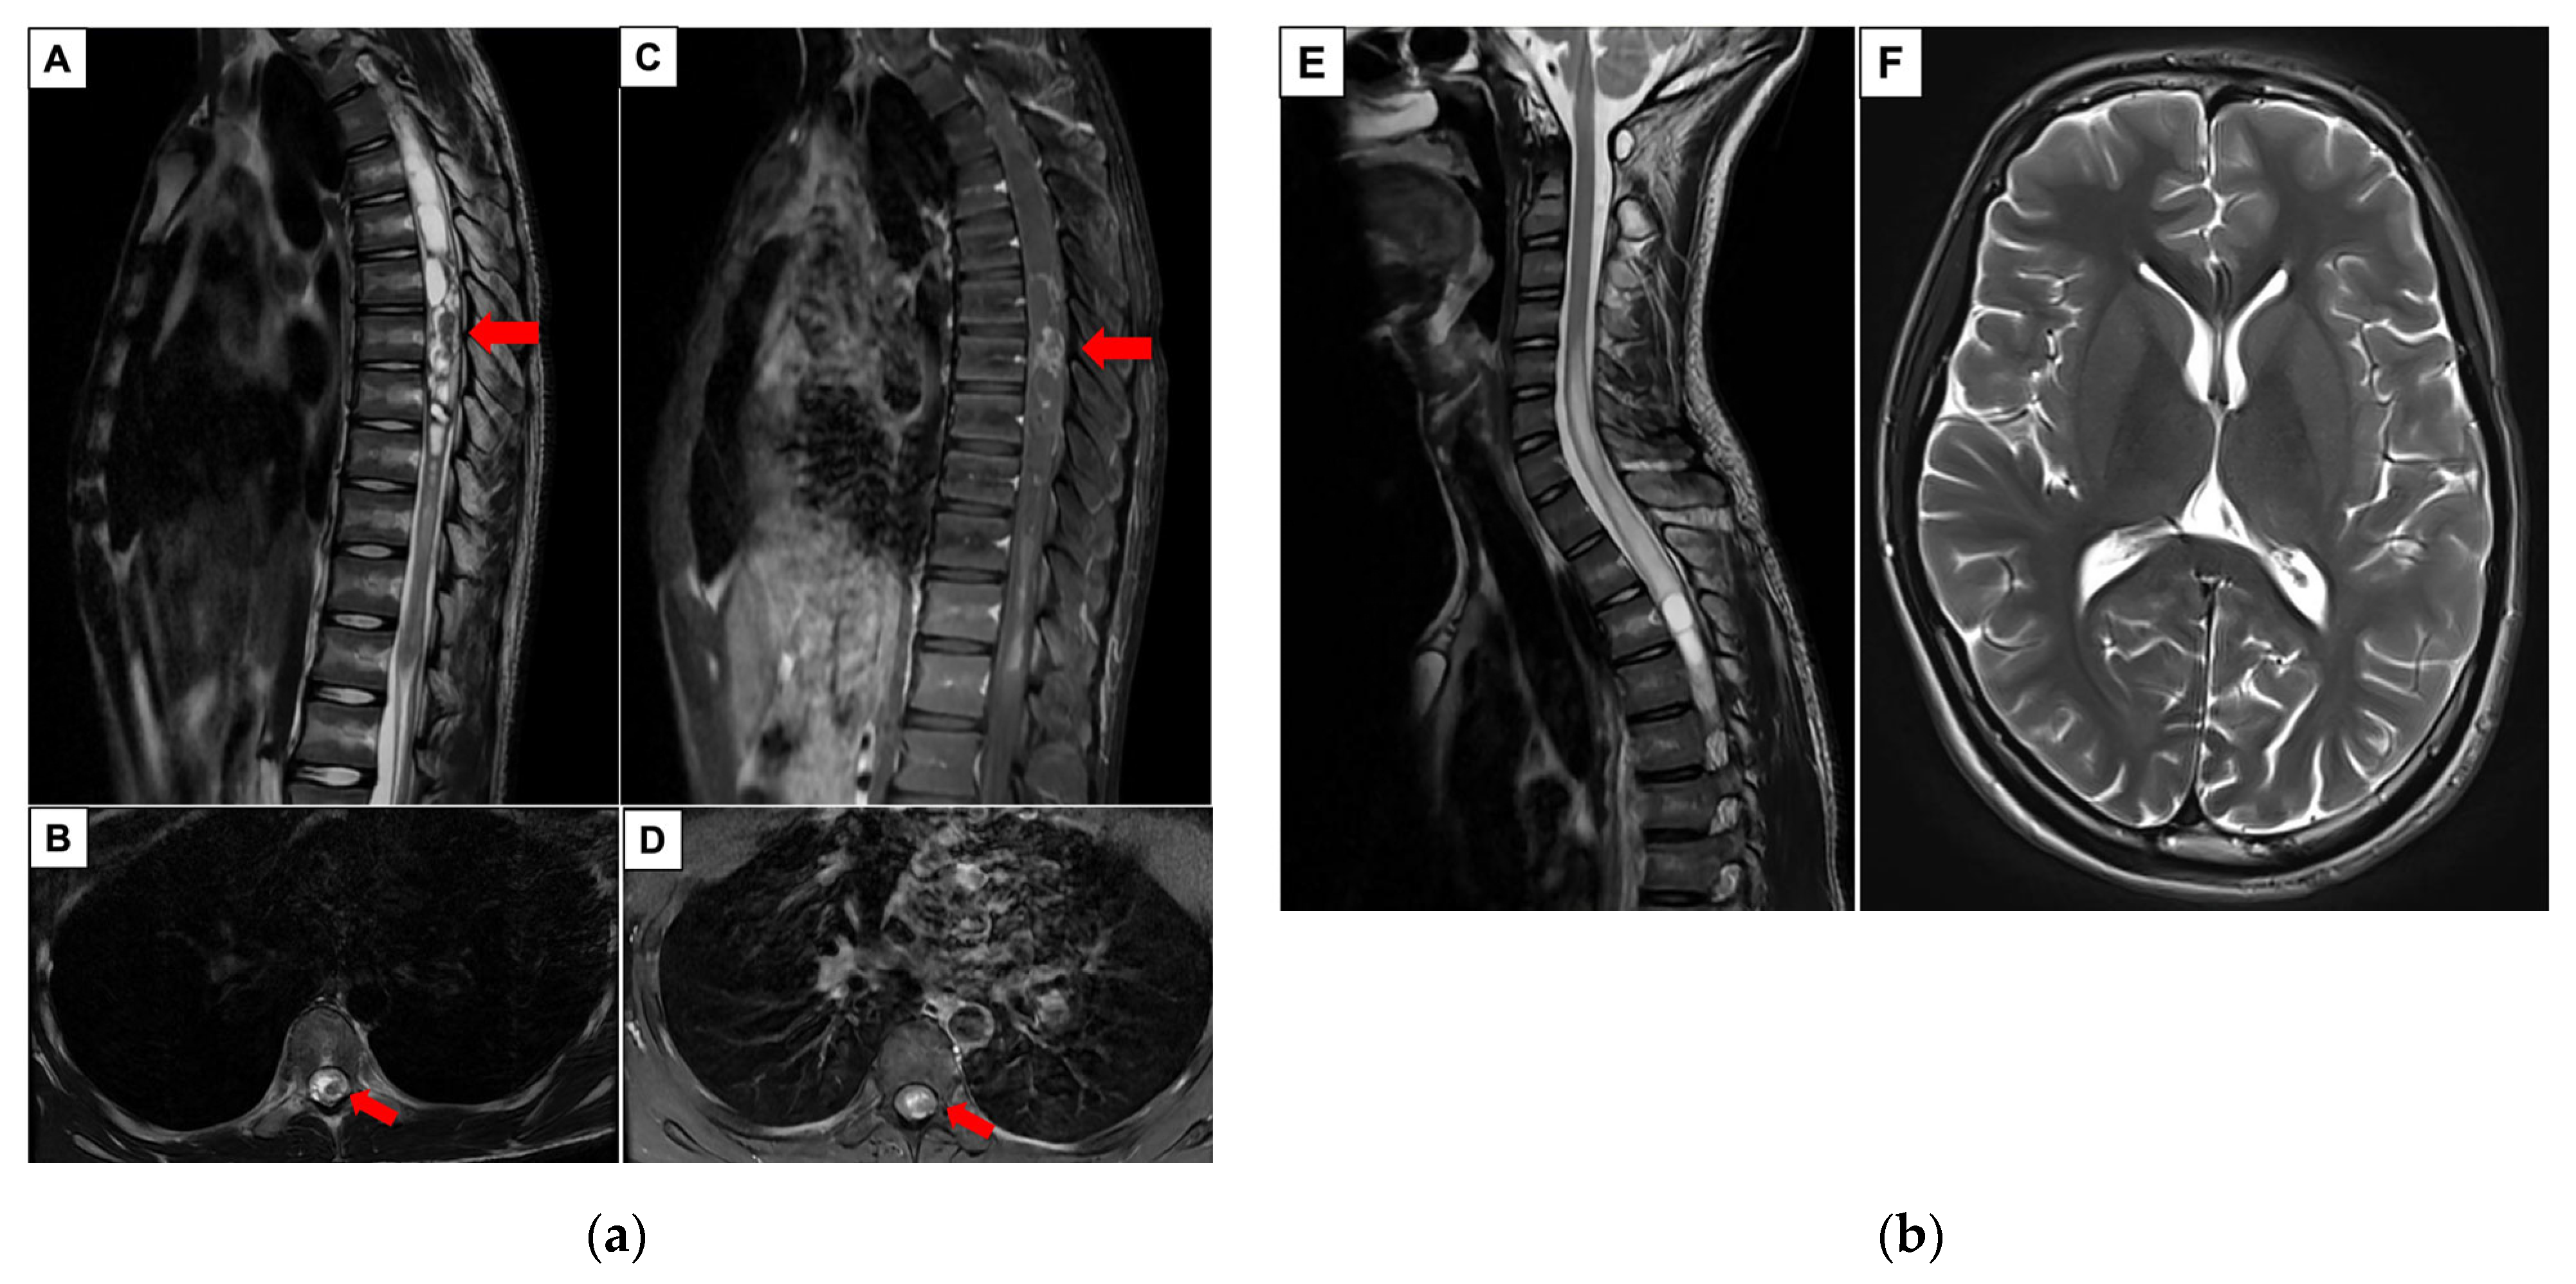

| 2025/our case | 1 | 17 | Intramedullary thoracic spine | FGFR1 p.K656E and V561M |